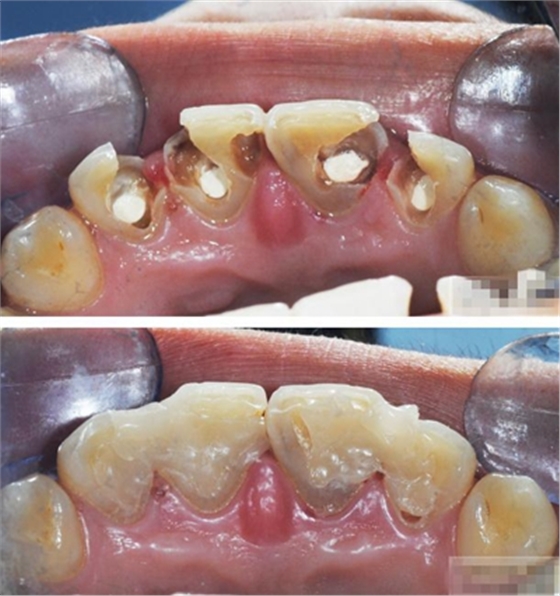

【主訴】上前牙充填物脫落兩個(gè)月

【病史】上前牙一年前行根管治療,充填物部分脫落,自覺(jué)影響美觀,從不敢笑,要求先行樹(shù)脂修復(fù)。(年齡:14歲)

【檢查】12,11,21,22,均行玻璃離子充填,各牙不同程度部分充填物脫落,探(—),叩(—),冷刺激無(wú)反應(yīng),無(wú)松動(dòng),牙齦顏色粉紅,質(zhì)地堅(jiān)實(shí)而有彈性,點(diǎn)彩正常,牙結(jié)石(—);牙髓活力測(cè)試無(wú)反應(yīng)。

【診斷】12,11,21,22牙體缺損